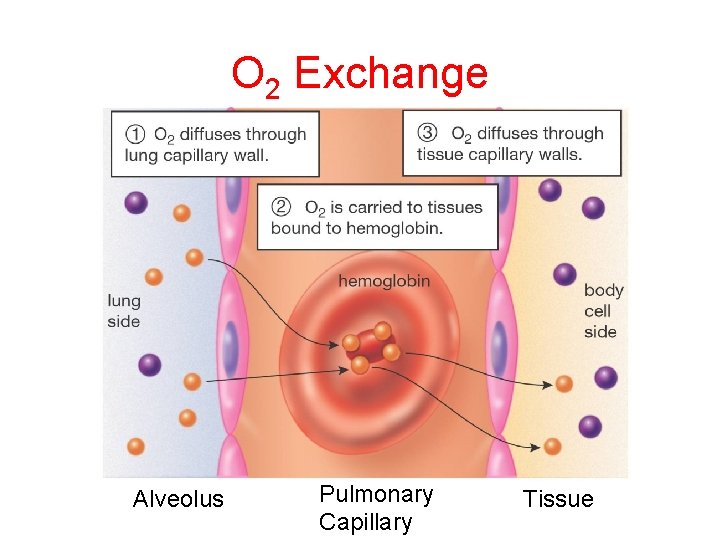

O 2 Exchange Alveolus Pulmonary Capillary Tissue